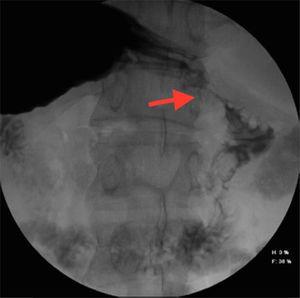

Paciente masculino de 57 años de edad, sin antecedentes de importancia. Refería dolor abdominal localizado en el epigastrio de moderada intensidad posterior a la ingesta de alimentos sólidos y posteriormente a líquidos, acompañado de náuseas y vómito, que le ocasionó desequilibrio hidroelectrolítico importante ameritando hospitalización, durante la cual se solicitaron estudios de laboratorio y gabinete, diagnosticando colecistitis crónica litiásica y coledocolitiasis por USG. Lesión infiltrante de la primera porción duodenal por endoscopia y proceso ulceroso por SEGD (fig. 1). Gas en la vesícula biliar, engrosamiento antro-pilórico y bulbo duodenal por tomografía computarizada (figs. 2 y 3); se solicitaron marcadores tumorales, los cuales se reportaron en rangos normales. El paciente fue sometido a laparotomía exploradora, encontrando inflamación crónica de la vesícula biliar, fistula colecistoduodenal con pérdida de la anatomía y páncreas anular (figs. 4 y 5), que no comprometía la integridad ni la permeabilidad duodenal, por lo que se realizó colecistectomía, desmantelamiento de la fístula y cierre primario de duodeno. El paciente evolucionó favorablemente; actualmente se encuentra en seguimiento por la clínica de cirugía hepatopancreatobiliar.